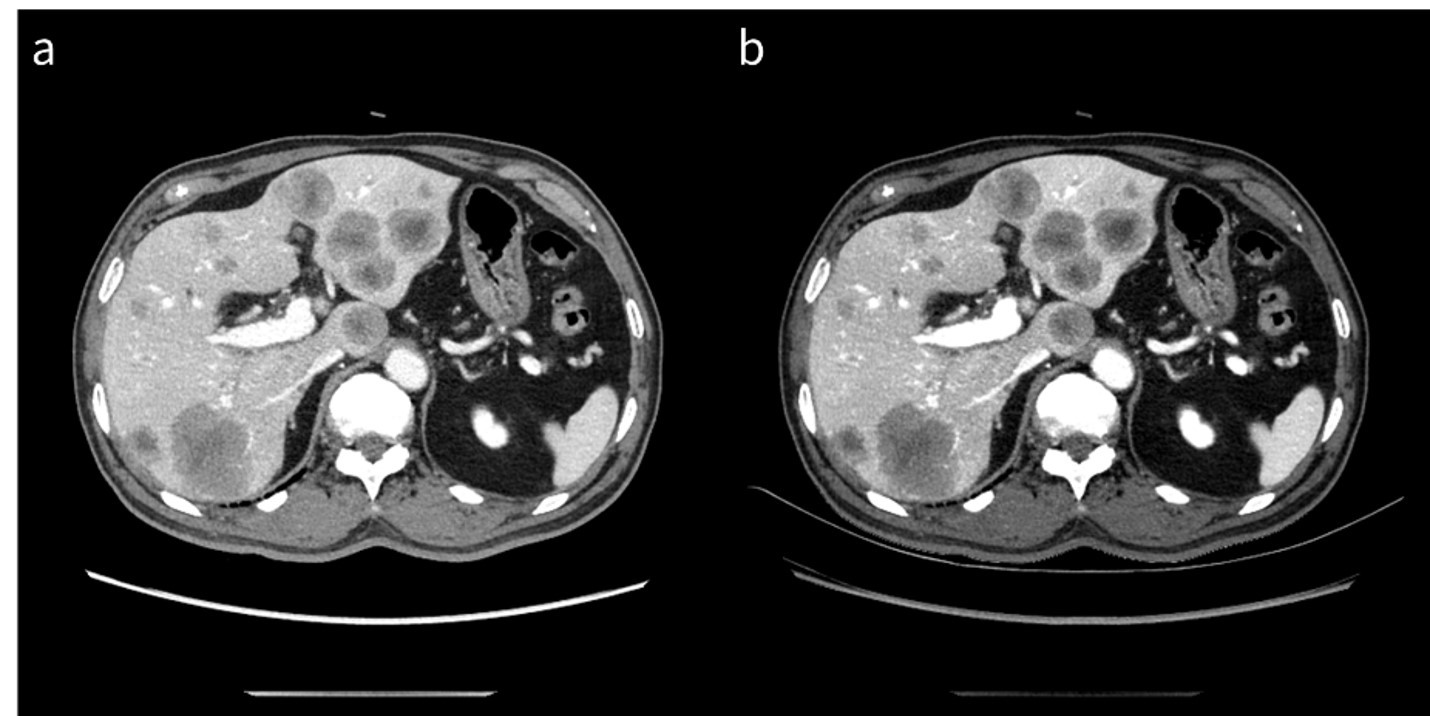

RevolutionApexElite_Gifu02_02.jpg

図1 膵癌の肝転移症例

a: 70 keV仮想単色X線画像

b: 40 keV仮想単色X線画像

40 keV仮想単色X線画像では、より肝転移巣と背景肝のコントラストが明瞭になっている。

これにより、低コントラスト病変の診断能向上にも一役買うことができ、日常診療では、診断能向上とまではいかなくとも、診断確信度を上げることのできる症例はそれなりの頻度で遭遇する(図2)。では、低keVの選択と言っても具体的に何keVを選択すればよいのだろうか。結論から言えば、何も考えずに最も低いエネルギーである40 keVの選択で構わない。40 keVを選択した場合、ノイズの上昇が気になるという声も聞こえてきそうだが、これもハードウェア・ソフトウェアの進歩によりノイズの気にならない、日常臨床で十分に使用できる画質感になっていると断言できる。